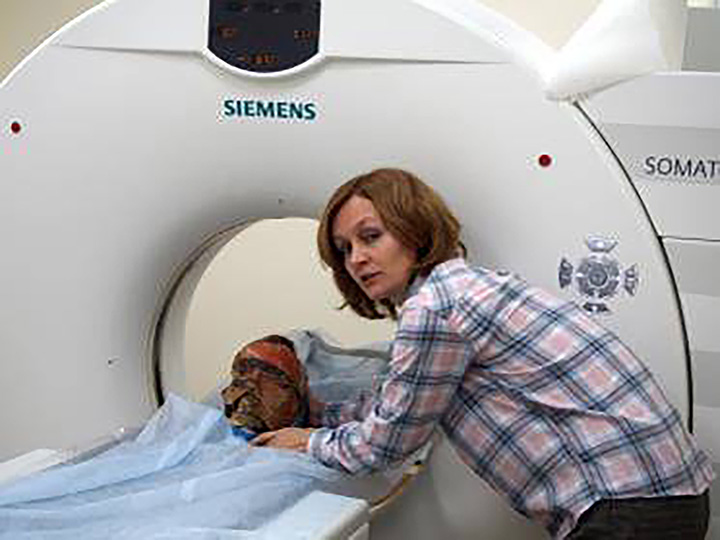

‘The computer scan allowed us to see, so to say, three layers – the layer of the mask, the layer of the face without the mask and layer of the skull.’ The face of the woman lying in the same burial chamber – also buried in a fur coat – has not been revealed with a CT scan.

‘I would really like to make CT scan of female mummified head,’ she said. I’m planning to find a clinic which can do this research and decipher it for us.’ For now, we do not know who the woman was and how she and the man were related.